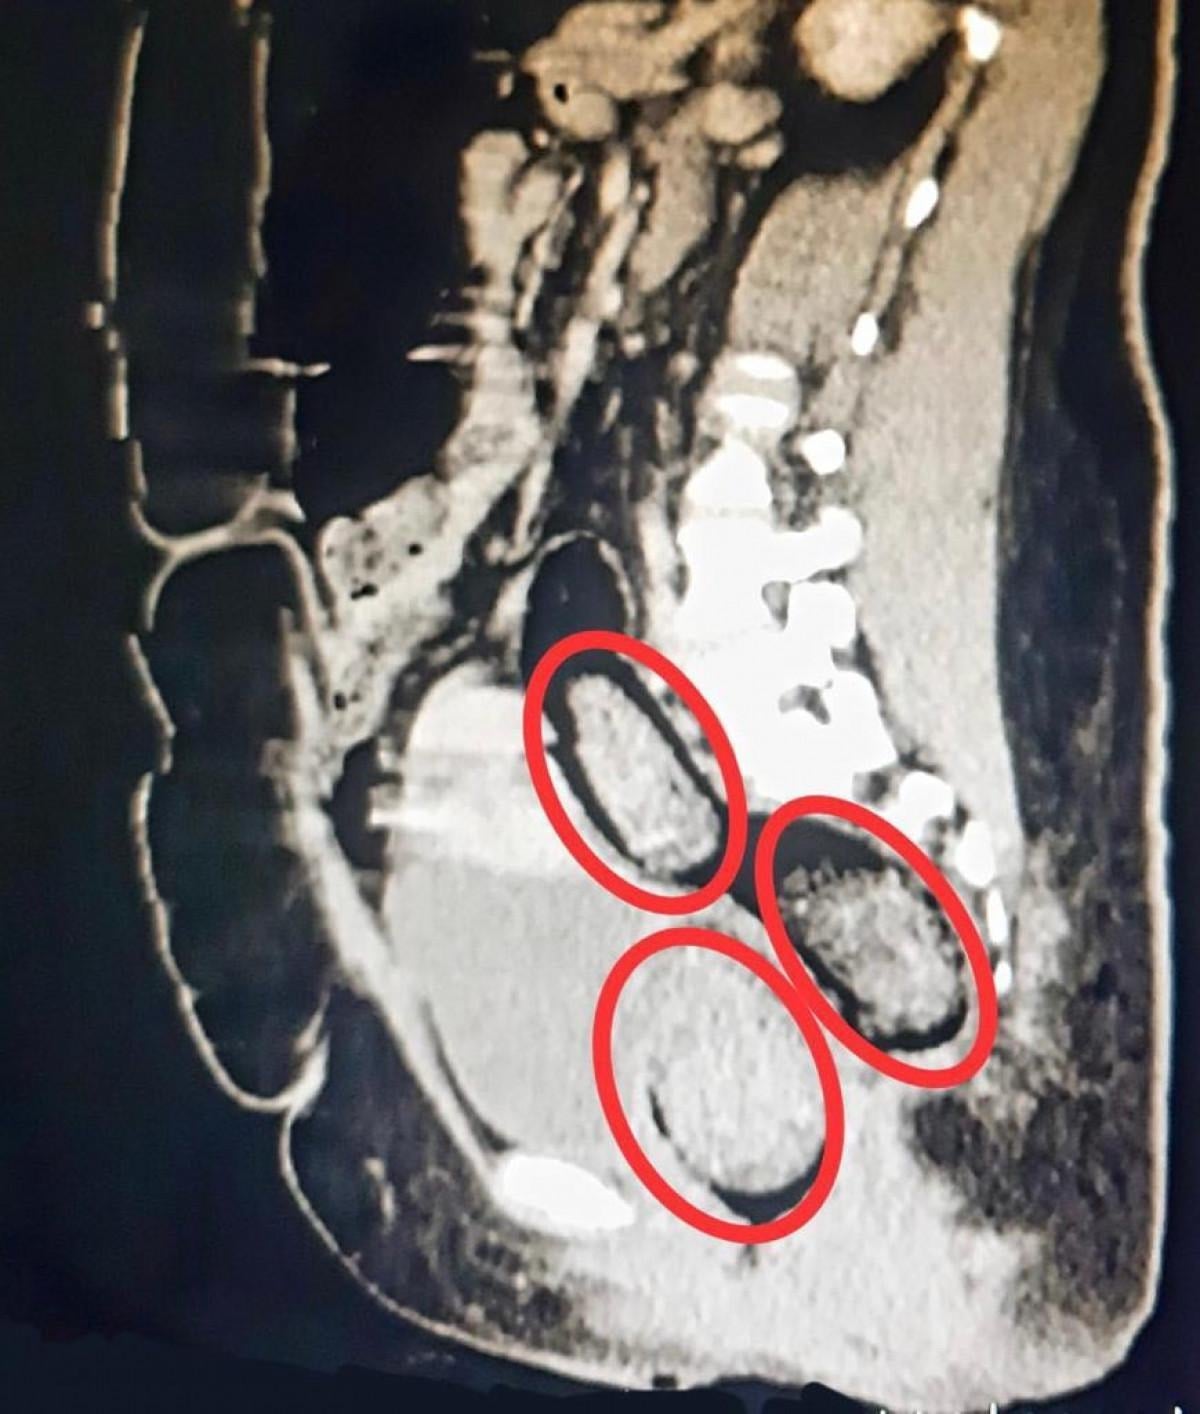

Kars Harakani Devlet Hastanesi'ne götürülen Aeınezad'a röntgen çekildi.

Yapılan incelemelerde makatında uyuşturucu tespit edildi.

Cerrahi operasyonla kadının makatından 3 parça halinde toplam 318 gram metamfetamin çıkarıldı.